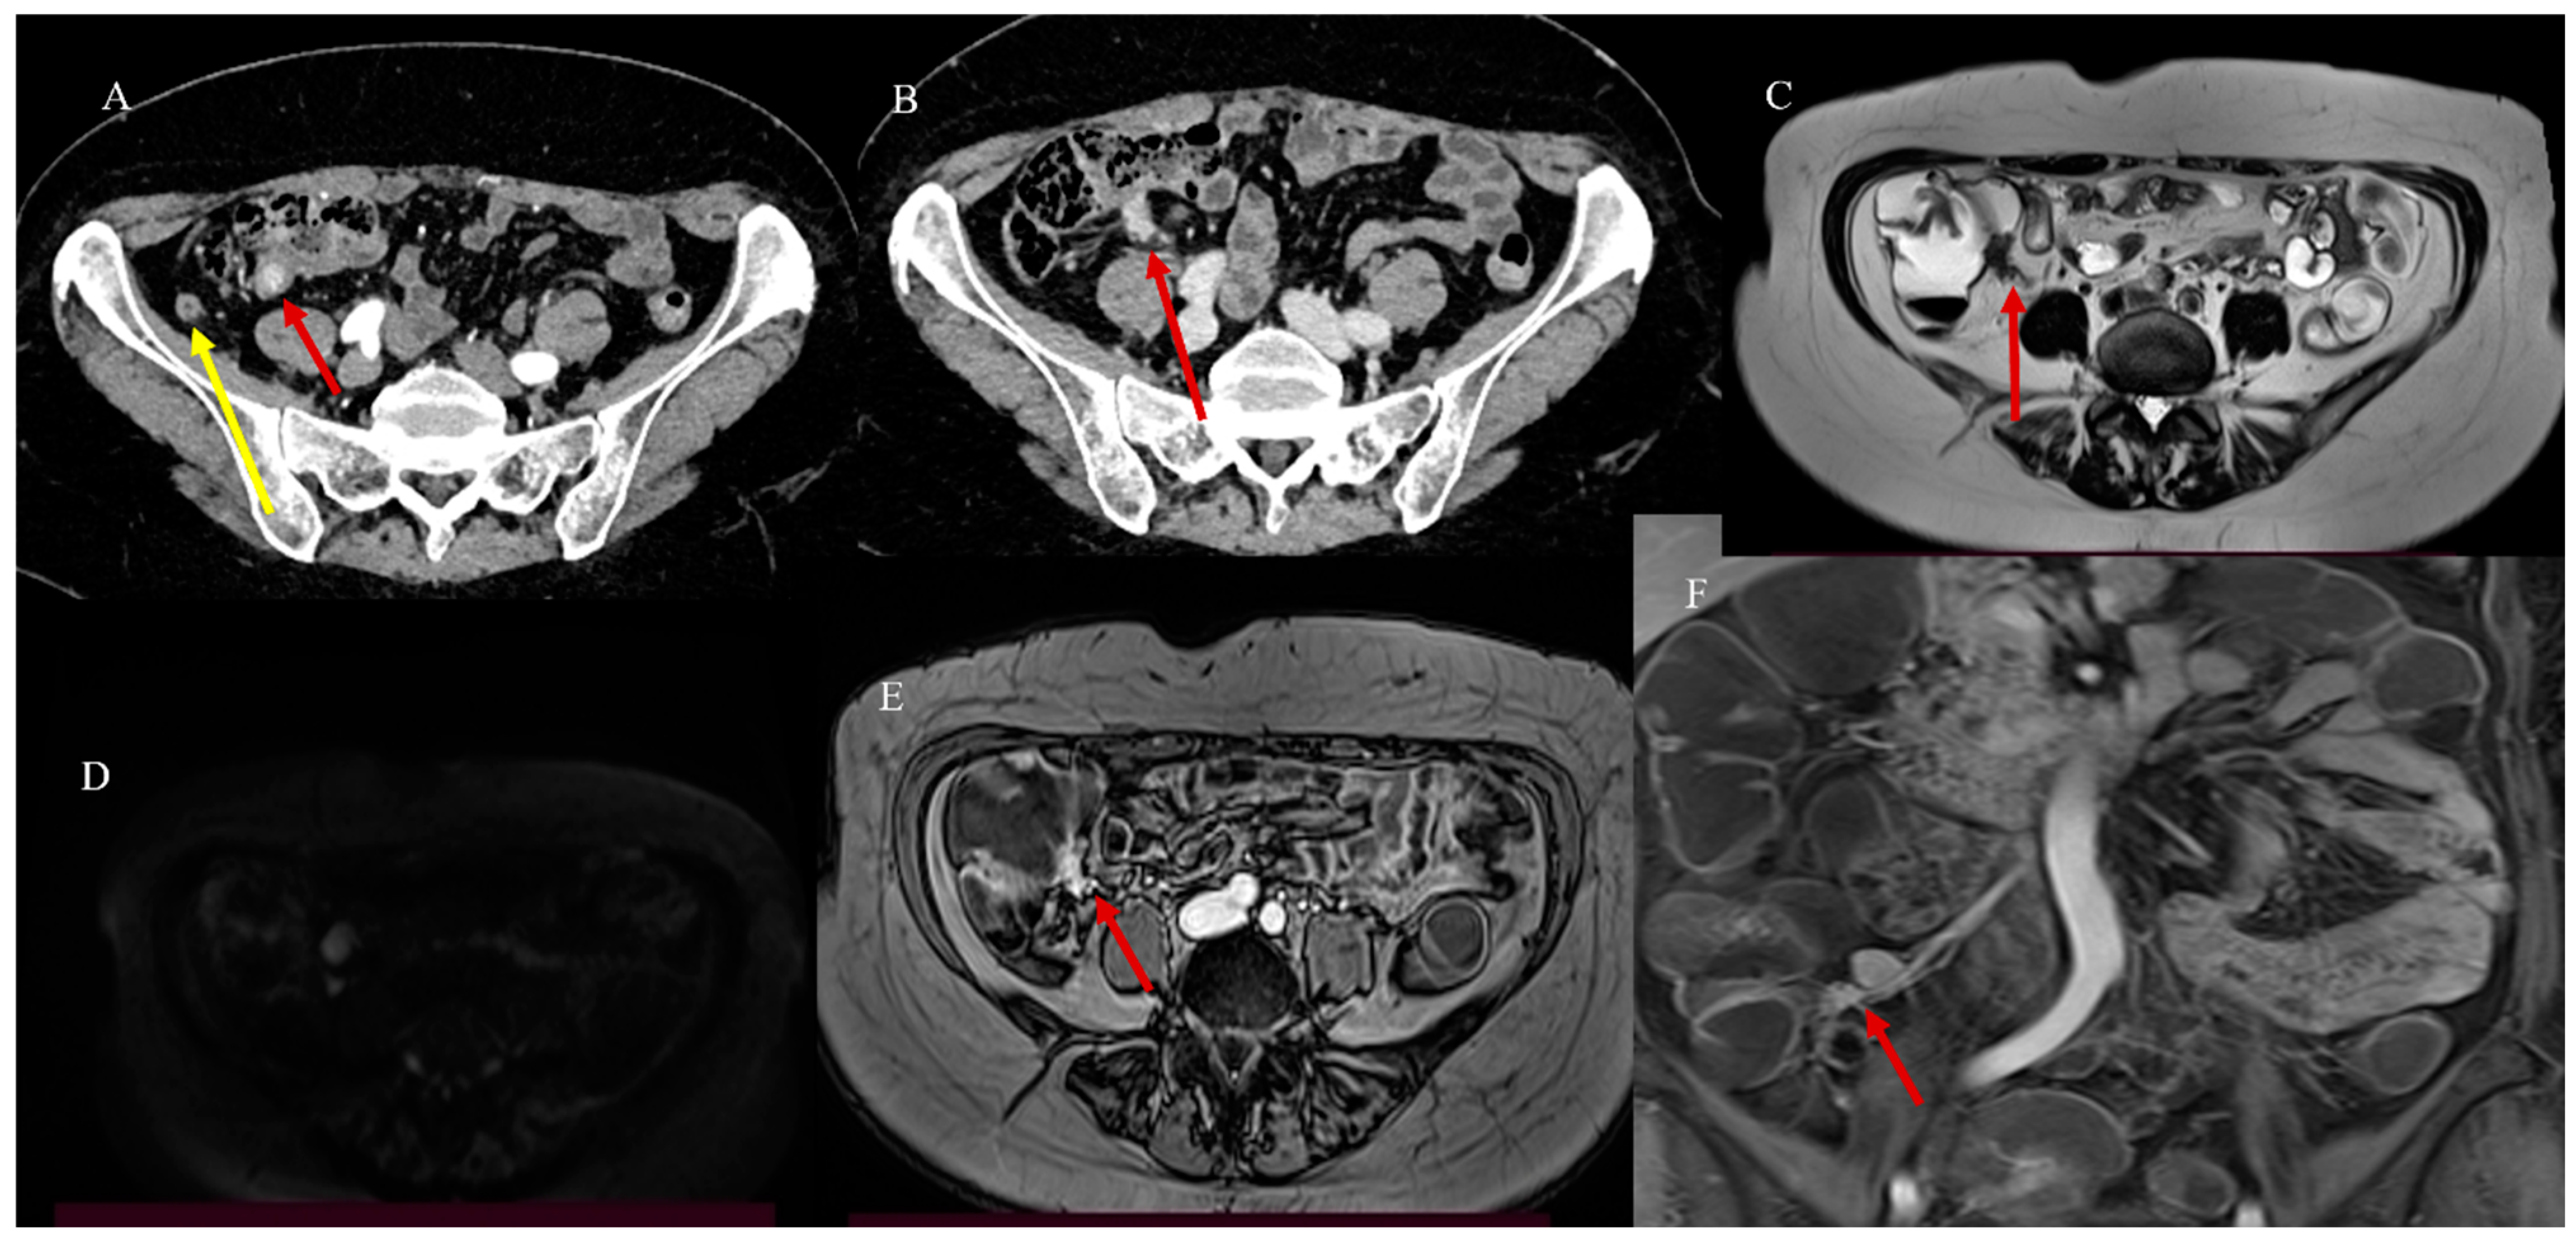

- Masselli, G.; Casciani, E.; Polettini, E.; Laghi, F.; Gualdi, G. Magnetic resonance imaging of small bowel neoplasms. Cancer Imaging 2013, 13, 92–99. [Google Scholar] [CrossRef] [PubMed]

- Faggian, A.; Fracella, M.R.; D’alesio, G.; Alabiso, M.E.; Berritto, D.; Feragalli, B.; Miele, V.; Iasiello, F.; Grassi, R. Small-Bowel Neoplasms: Role of MRI Enteroclysis. Gastroenterol. Res. Pract. 2016, 2016, 9686815. [Google Scholar] [CrossRef]

- Boone, D.; Taylor, S.A. Magnetic Resonance of the Small Bowel: How to Do It. Magn. Reson. Imaging Clin. N. Am. 2019, 28, 17–30. [Google Scholar] [CrossRef] [PubMed]

- Maccioni, F.; Busato, L.; Valenti, A.; Cardaccio, S.; Longhi, A.; Catalano, C. Magnetic resonance imaging of the gastrointestinal tract: Current role, recent advancements and future prospectives. Diagnostics 2023, 13, 2410. [Google Scholar] [CrossRef] [PubMed]

- Biondi, M.; Bicci, E.; Danti, G.; Flammia, F.; Chiti, G.; Palumbo, P.; Bruno, F.; Borgheresi, A.; Grassi, R.; Grassi, F.; et al. The role of magnetic resonance enterography in crohn’s disease: A review of recent literature. Diagnostics 2022, 12, 1236. [Google Scholar] [CrossRef]

- Reda, A.M.; Saleh, R.A.; Elgawish, M.A.; Elsharkawy, A. MR enterography in small bowel diseases, adding multipoint Dixon sequence, is it worth? Egypt. J. Radiol. Nucl. Med. 2023, 54, 87. [Google Scholar] [CrossRef]

- Lu, J.; Zhou, Z.; Morelli, J.N.; Yu, H.; Luo, Y.; Hu, X.; Li, Z.; Hu, D.; Shen, Y. A systematic review of technical parameters for MR of the small bowel in non-IBD conditions over the last ten years. Sci. Rep. 2019, 9, 14100. [Google Scholar] [CrossRef]

- Maccioni, F.; Alfieri, G.; Assanto, G.M.; Mattone, M.; Silveri, G.G.; Viola, F.; De Maio, A.; Frantellizzi, V.; Di Rocco, A.; De Vincentis, G.; et al. Whole body MRI with Diffusion Weighted Imaging versus 18F-fluorodeoxyglucose-PET/CT in the staging of lymphomas. Radiol. Med. 2023, 128, 556–564. [Google Scholar] [CrossRef]

- Pezzella, M.; Brogna, B.; Romano, A.; Torelli, F.; Esposito, G.; Petrillo, M.; Romano, F.; Di Martino, N.; Reginelli, A.; Grassi, R. Detecting a rare composite small bowel lymphoma by Magnetic Resonance Imaging coincidentally: A case report with radiological, surgical and histopathological features. Int. J. Surg. Case Rep. 2018, 46, 50–55. [Google Scholar] [CrossRef]